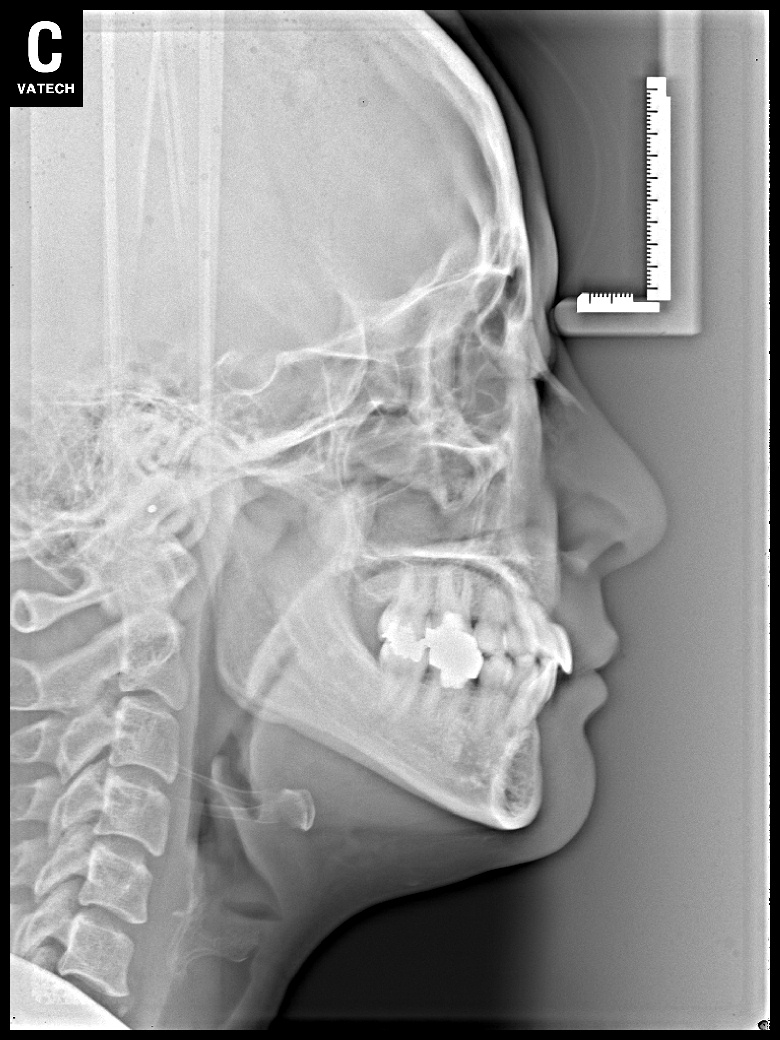

치료 전 사진입니다.